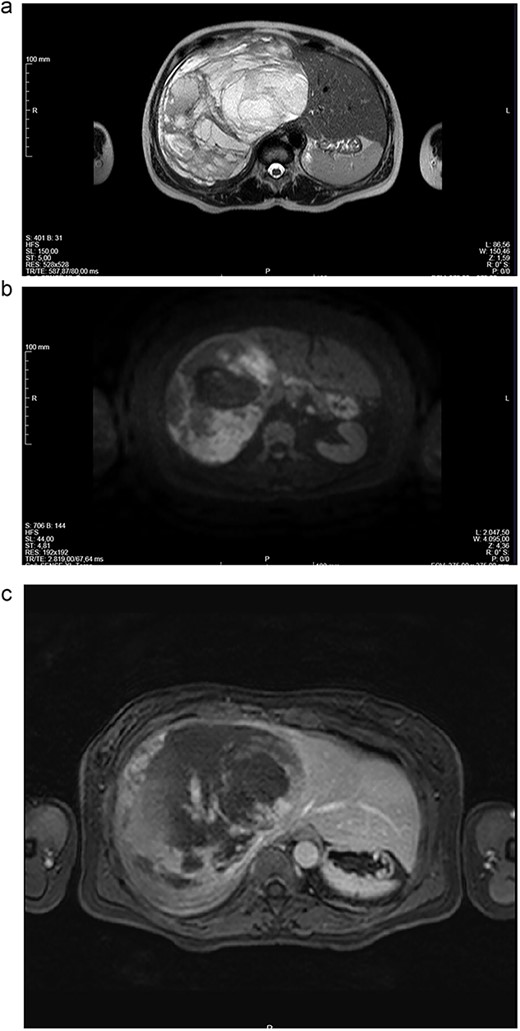

Abdominal CT (Fig. 1a and b) and MRI (Fig. 2a and b) showed a 18 × 12 × 20 cm3 lobulated cystic mass with thin enhancing septa in the right lobe of the liver with fluid levels suggesting atypical hemangioma. The right hepatic vein not dissociable to the tumor (Fig. 2c).

(a-c) Magnetic resonance imaging (MRI) scans of a woman aged 49 years with undifferentiated embryonal sarcoma of the liver. Liver of increased dimensions, due to the presence of a voluminous oval mass and well-defined limits occupying the entire right lobe. Heterogeneous mass with enhanced thin septa in the right lobe of the liver with fluid levels suggestive of atypical hemangioma. The right hepatic vein not dissociable to the tumor.

Given the symptomatology, dimensions and potential risk of complications (spontaneous rupture with hemoperitoneum), surgical treatment was proposed. Right hepatectomy was performed since the right hepatic vein not dissociable to the tumor (Fig. 2c).